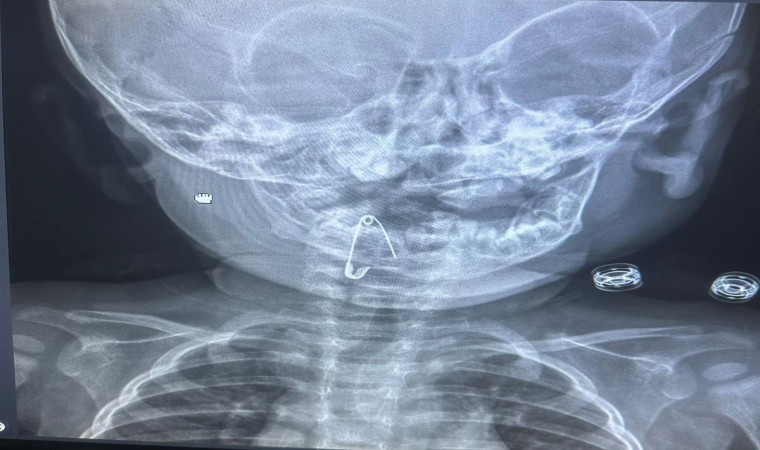

Güroymak ilçesinde 8 aylık bebek, evde bulunan çengelli iğneyle oynarken onu yuttu. Öksürmeye başlayan minik çocuğun, hastanede çekilen röntgen sonucu çengelli iğneyi yuttuğu fark edildi. Güroymak Devlet Hastanesi’nden Tatvan Devlet Hastanesi’ne ambulansla sevki gerçekleşen minik çocuk, Kulak Burun Boğaz Hastalıkları Uzmanı Operatör Dr. Hakan Tuhan tarafından yapılan başarılı operasyonla sağlığına kavuştu. Çengelli iğnenin saplı olduğu soluk borusundan çıkarılan bebek, 2 saatlik gözlemin ardından taburcu edildi.

Konuyla ilgili açıklamada bulunan Kulak Burun Boğaz Hastalıkları Uzmanı Operatör Dr. Hakan Tuhan, “8 aylık bir bebek, Bitlis’in Güroymak ilçesinden tarafımıza danışıldı. Güroymak ilçesinde çekilen röntgen sonucunda çengelli iğnenin soluk borusunun girişinde olduğunu teyit ettik. Yapılan müdahaleler sonucunda çengelli iğneyi çıkardık. Çıkardıktan sonra iki saat kadar gözlem altında tuttuk hastamızı. Daha sonrasında herhangi bir komplikasyonla karşılaşmadık ve sorunsuz bir şekilde taburcu ettik” dedi.